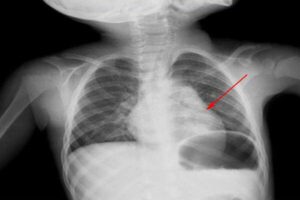

Что такое острая пневмония у ребенка

Острая пневмония — это инфекционное поражение легких, сопровождающееся инфильтративными изменениями тканей и поражением нижних дыхательных путей. Данная патология чаще всего диагностируется у детей до 3 лет (20 на 1000 случаев), у детей старшего возраста частота инфекций ниже (5-6 на 1000 случаев). Пневмония чаще всего возникает во время сезонных эпидемий ОРЗ. В чем опасность этой патологии? …